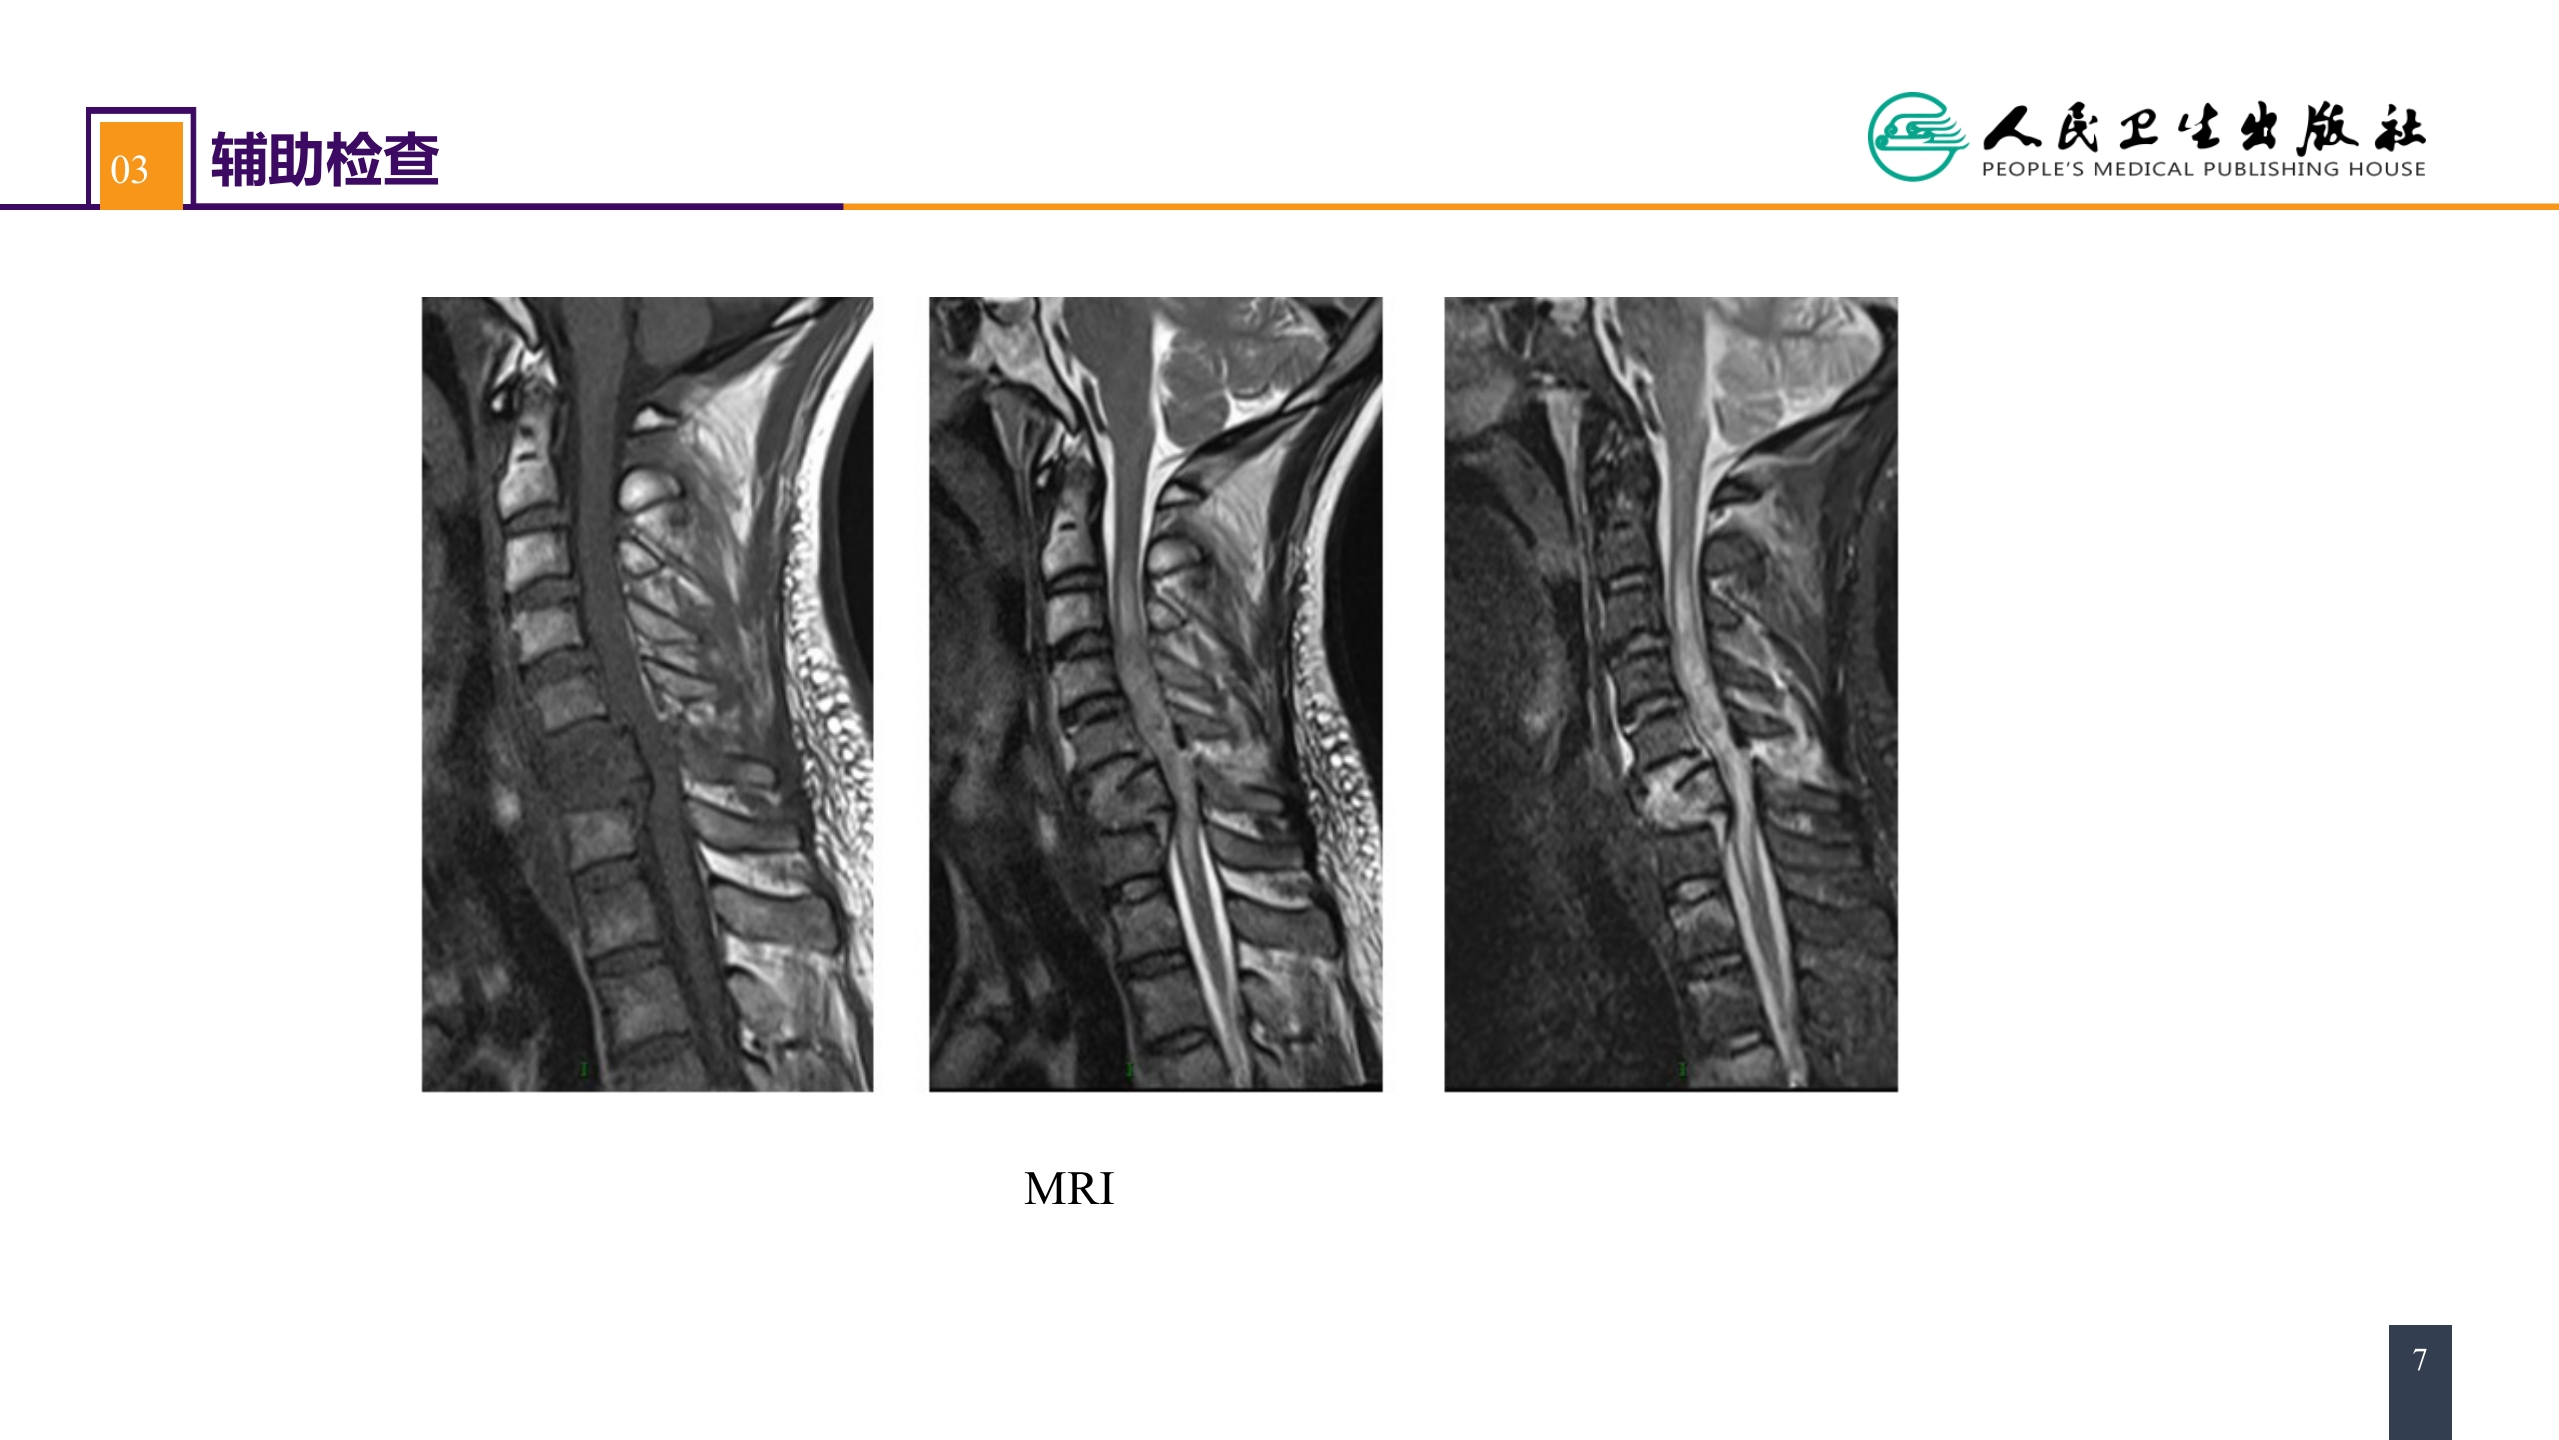

第六十二章 案例分析-颈椎骨折伴脊髓损伤